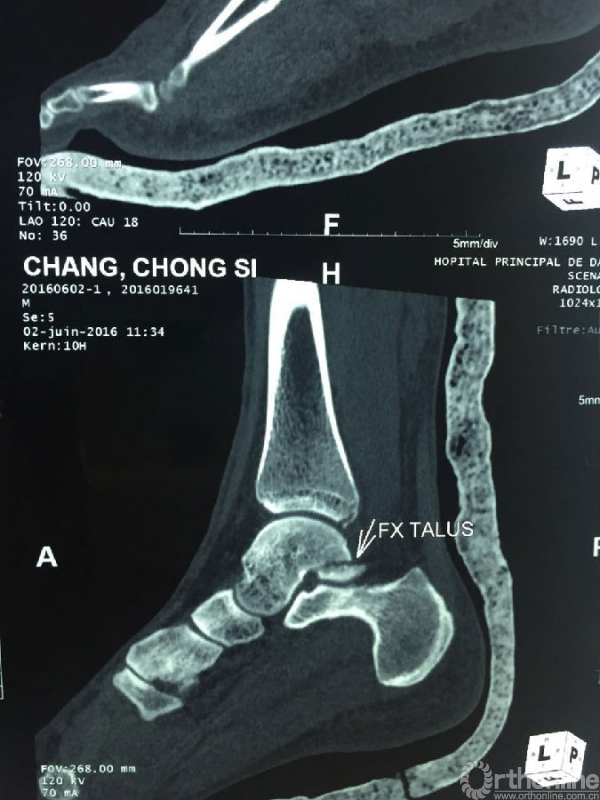

战士司崇昶,因31日的爆炸恐怖袭击导致全身多处创伤,左耳廓、颌面部炸伤,左踝开放性粉碎性骨折,面部及左下肢神经损伤。在初步清创缝合包扎后转入ICU病房。杨润功教授到达ICU病房后,仔细询问了病情,查看伤口情况,重新给予下肢石膏固定,并详细叮嘱康复锻炼要点。目前司崇昶生命体征平稳,饮食状态已有所好转。

司崇昶踝关节CT